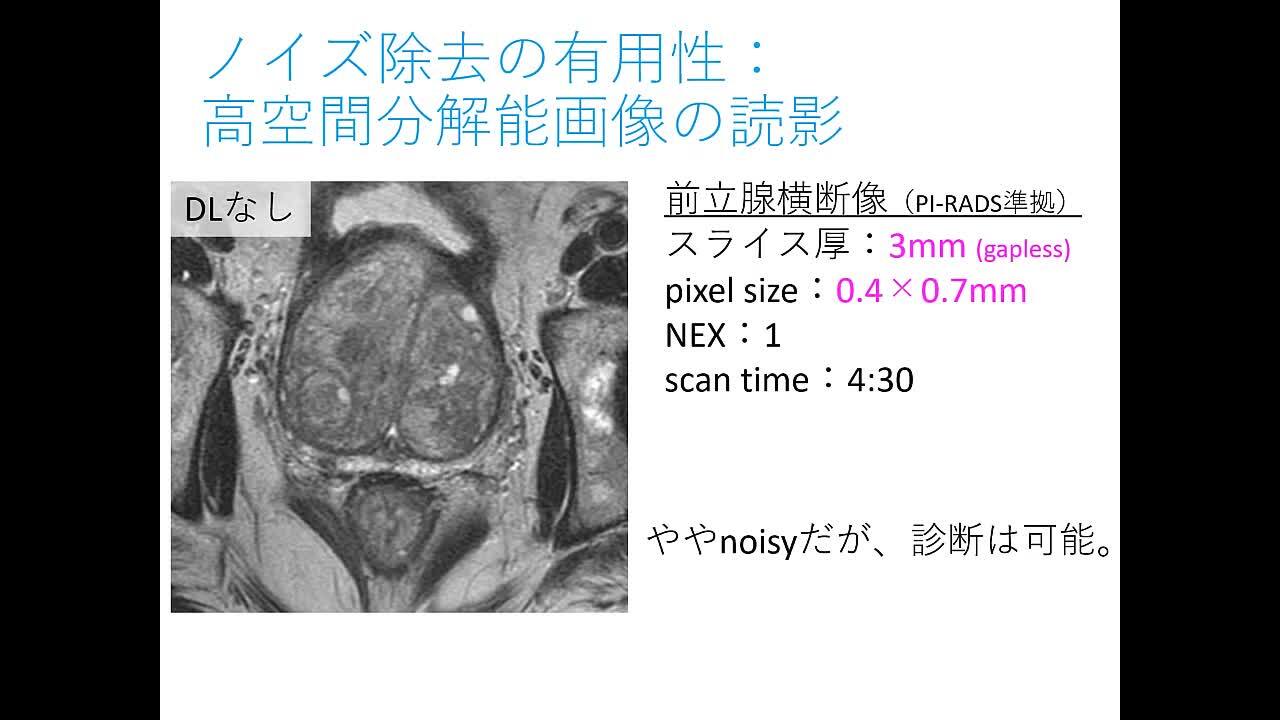

Radiology Review Manual (Dahnert, Radiology Review Manual。放射線療法および診断イメージング | Mirion。Gastrointestinal Imaging Q&A for the Radiology Boards。こな納豆 sonomono。UFZR7CQ2QVP55HCFFWCXAVYWBI.jpg。静岡がんセンター × Multiple Brain Mets SRS(ブレインラボ)。書き込み、折り込みなどございません。。Radiology Review Manual on the App Store。Radiology Review Manual - Apps on Google Play。坪山 尚寛 先生 大阪大学大学院医学系研究所 放射線医学講座。放射線科 | 医療法人真生会向日回生病院。Radiology Review Manual 8th edition放射線レビューマニュアル 第8版購入したもののほぼ未使用のまま保管しており、出品いたします。Radiology Review Manual (Dahnert, Radiology Review Manual。Radiology Review Manual: 9781496360694: Medicine & Health。eBookのためのコードも未使用です(写真参照)表面にわずかにすれあります。radiology-review-manual.jpg